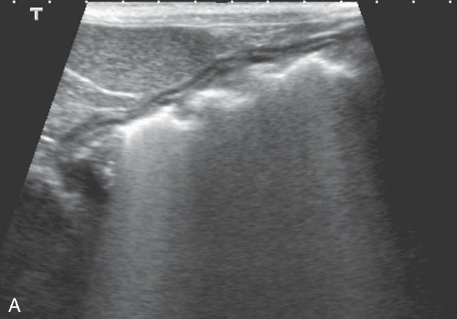

Edge Shadowing

most common with round fluid filled structures

occurs at edge parallel to the sound beam

causes a dark shadow from edge of structure

gallbladder, urinary bladder, cysts, and sometimes kidneys